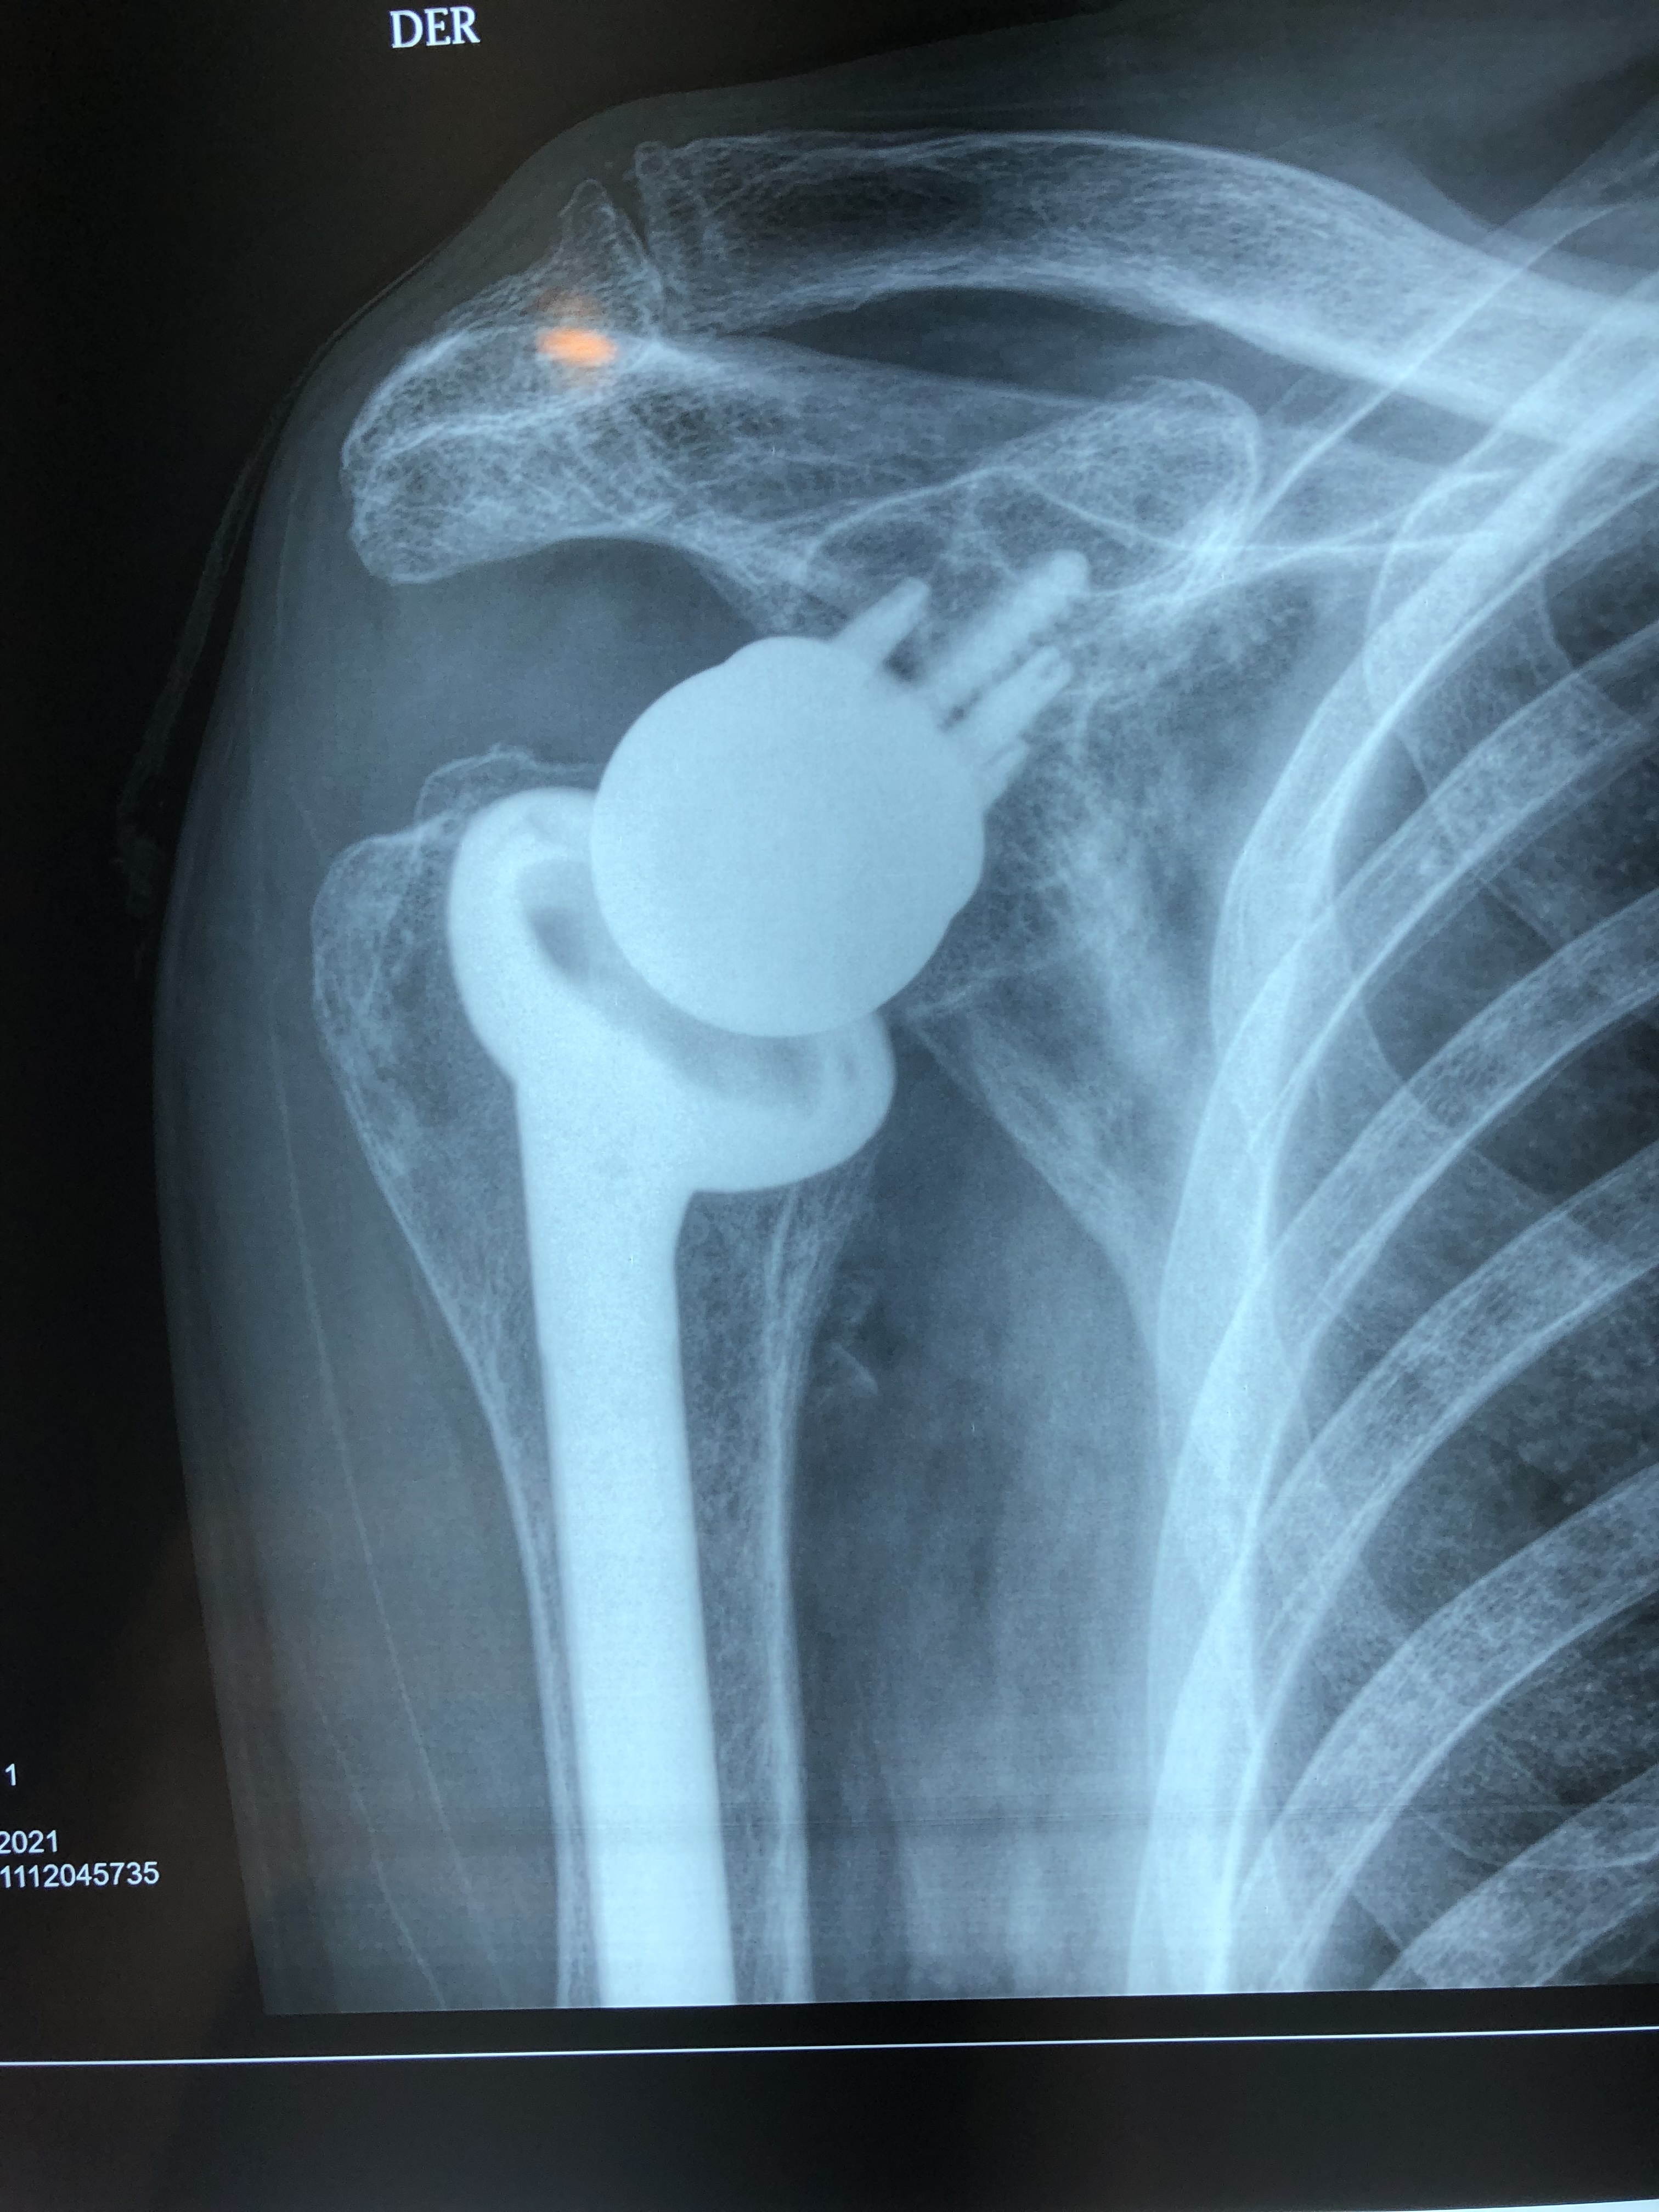

Prótesis Reversa De Hombro

Paquete de Cirugía: Prótesis Reversa de Hombro

¿Qué es la cirugía de prótesis reversa de hombro?

La prótesis reversa de hombro es una cirugía especializada que se utiliza cuando el manguito rotador está muy dañado o irreparable.

A diferencia de una prótesis tradicional, esta inversión del diseño permite que otros músculos (principalmente el deltoides) compensen la falta del manguito rotador, logrando:

Mayor estabilidad

Más fuerza para elevar el brazo

Disminución importante del dolor

Es ideal en casos de artropatía por manguito rotador, fracturas complejas o fallas de cirugías previas.